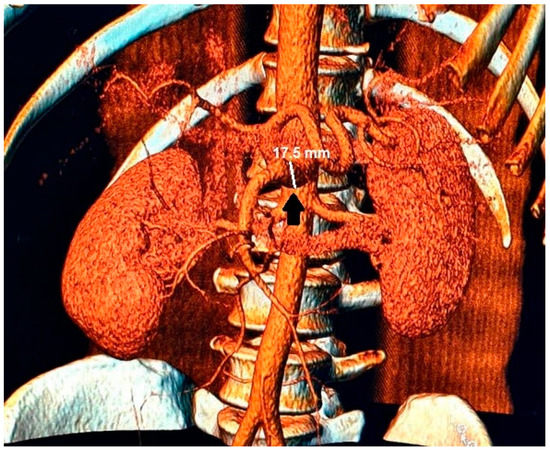

Figure 3.

In the 3D reconstruction of CT scan images, the enlarged celiac-mesenteric trunk can be observed indicated by a black arrow.

By comparing previous and current imaging tests, an increase of 5 mm in CMT diameter in 5 years was observed.